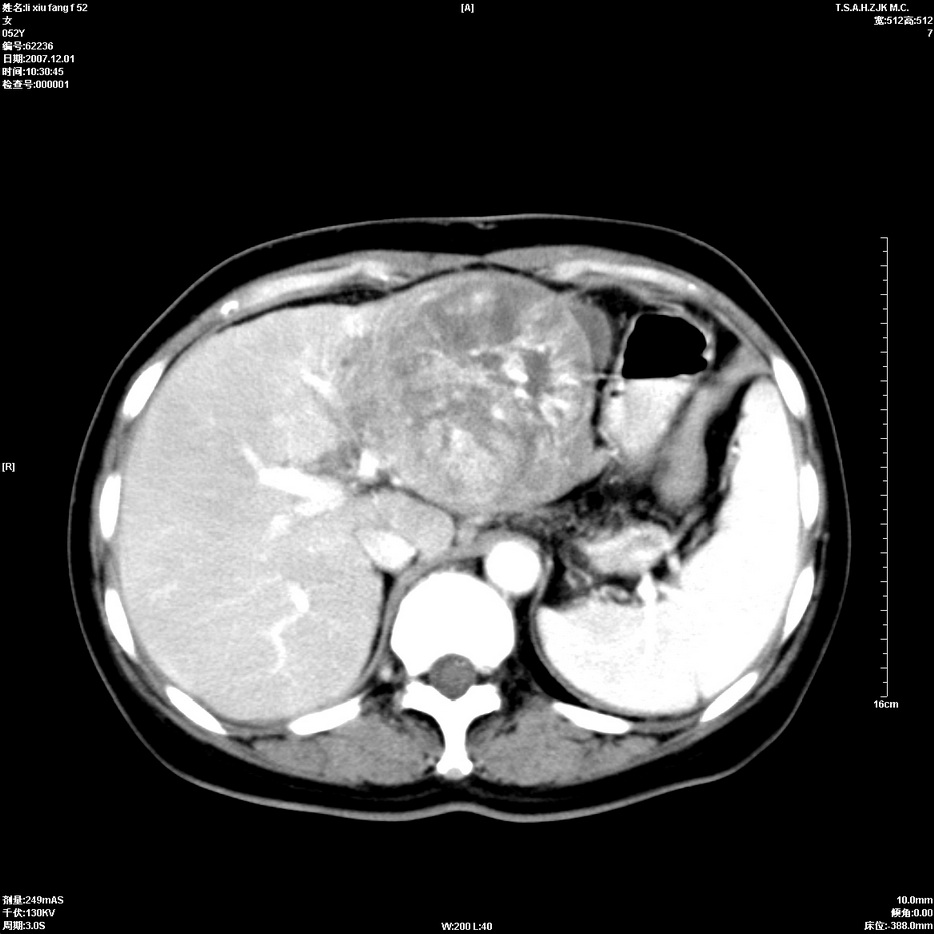

标题: CT12858:女,52岁,胎甲球蛋白861肝左叶占位,肝癌。下腔静 [打印本页]

标题: CT12858:女,52岁,胎甲球蛋白861肝左叶占位,肝癌。下腔静

肝左叶巨大低密度灶肿块,增强符合快进快出表现,有动静脉交通支;静脉期,下腔静脉内有充盈缺损,afp明显升高,支持肝癌并下腔静脉癌栓形成。

支持楼主   门静脉主干及左支癌栓形成

以下是引用拾荒者在2008-4-15 22:57:00的发言:[br]肝左叶巨大低密度灶肿块,增强符合快进快出表现,有动静脉交通支;静脉期,下腔静脉内有充盈缺损,afp明显升高,支持肝癌并下腔静脉癌栓形成。